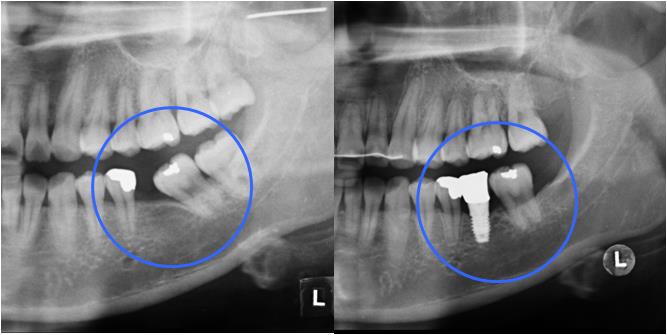

ºÎÁ¤±³ÇÕÀÌ Æ¯Á¤ ºÎÀ§¿¡ ±¹ÇѵǾî ÀÖ´Â °æ¿ì ƯÁ¤ Ä¡¾Æ¿¡¸¸ ÀåÄ¡¸¦ ºÎÂøÇÏ¿© ±³Á¤ ÇÏ´Â °æ¿ìµµ ÀÖ½À´Ï´Ù. Ʋ¾îÁ®ÀÖ´Â ¾Õ´Ï¸¸ ºÎºÐÀûÀ¸·Î °í¸£°Ô ¹è¿Çϰųª(±×¸²3) º¸Ã¶(ÀÓÇöõÆ®)À» À§ÇØ ¾²·¯Áø ¾î±Ý´Ï¸¦ ¹Ù·Î ¼¼¿ì´Â °æ¿ì(±×¸²4), »ó½ÇµÈ ´ëÇÕÄ¡ ¶§¹®¿¡ Á¤ÃâµÈ ¾î±Ý´Ï¸¦ ¾ÐÇϽÃŰ´Â Ä¡·á°¡ ´ëÇ¥ÀûÀÎ °æ¿ìÀÔ´Ï´Ù(±×¸²5). Áõ·ÊÀÇ ³À̵µ³ª ¹è¿»óÅ¿¡ µû¶ó Åë»ó 6°³¿ù ³»¿ÜÀÇ ±â°£ÀÌ ÇÊ¿äÇÕ´Ï´Ù.

| | ±×¸²4 |

|